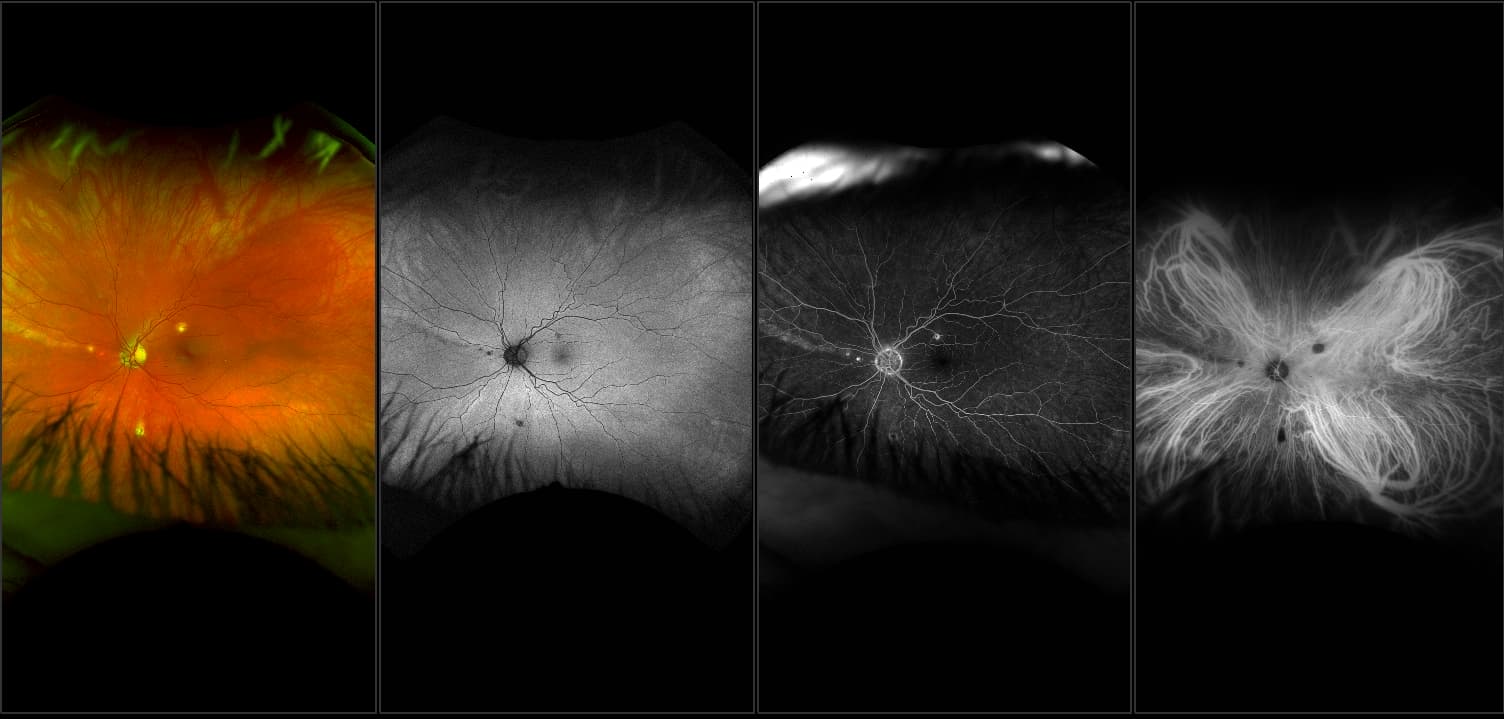

Silverstone - Branch Retinal Vein Occlusion with Disciform Scar, RG, FA, OCT

Branch retinal vein occlusion can be caused by thrombosis but is more likely to be produced by compression due to arteriolosclerosis. This occurs at arteriovenous crossing sites where there is a common adventitial sheath of each vessel. Marked A/V nicking usually precedes the occlusive process.